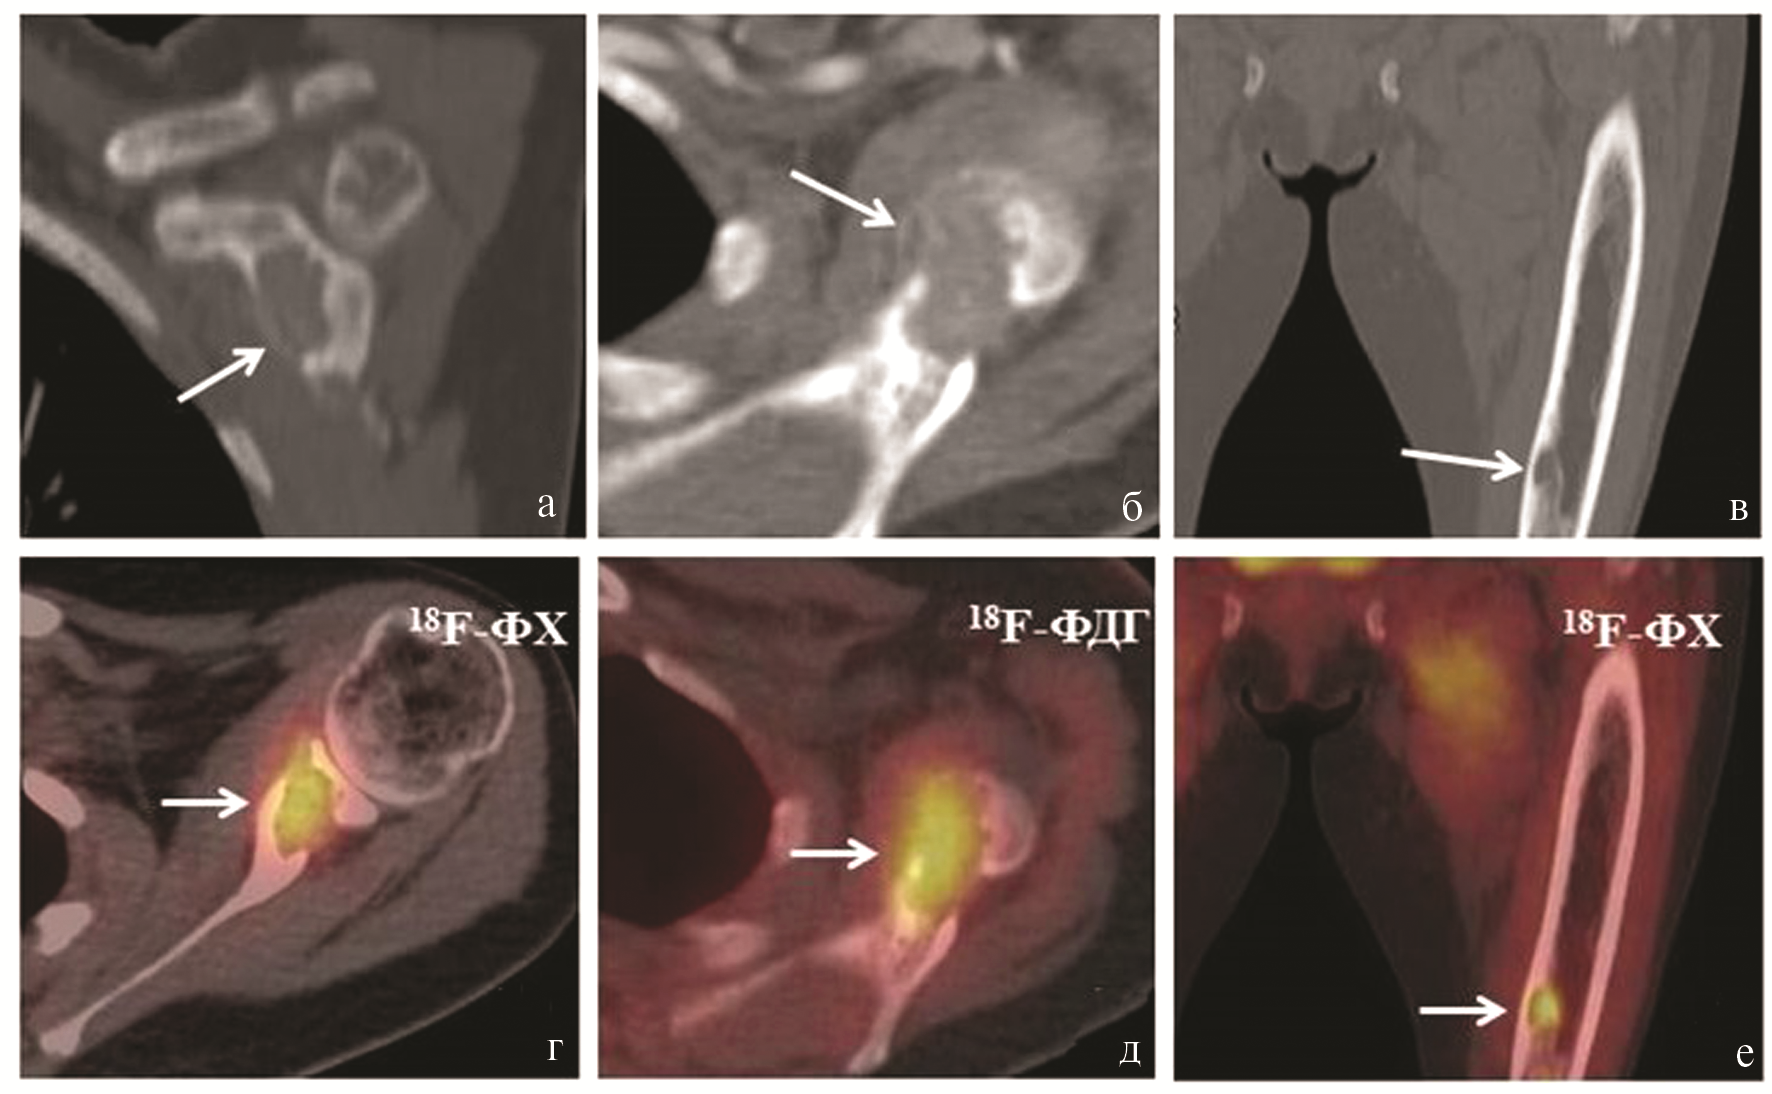

Выявлены множественные очаги патологического накопления обоих РФП в костях, которые соответствовали по КТ разнокалиберным очагам литической деструкции, с замещением нормальной костной ткани патологической, с деструкцией кортикальных слоев («бурые опухоли») и участкам уплотнения (фиброз) костного мозга в длинных трубчатых костях. Накопление 18F-ФДГ и 18F-ФХ во всех костных очагах было примерно одинаковым (макс. SUV от 2,74 до 6,55). Для демонстрации мы выбрали два очага — в акромиальном отростке левой лопатки и средней трети левой бедренной кости (рис. 2, на цв. вклейке).

Рис. 2. Результаты лучевой диагностики пациентки В. (стрелками указаны патологические очаги в костях).

а — очаг литической деструкции в левой лопатке по КТ (фронтальный срез); б — этот же очаг в левой лопатке по КТ (аксиальный срез); в — очаг литической деструкции в средней трети диафиза левой бедренной кости по КТ (фронтальный срез); г — очаг патологического накопления 18F-ФХ в левой лопатке (совмещенный ПЭТ/КТ, аксиальный срез); д — очаг патологического накопления 18F-ФДГ в левой лопатке (совмещенный ПЭТ/КТ, аксиальный срез); е — очаг патологического накопления 18F-ФХ в средней трети левой бедренной кости (совмещенный ПЭТ/КТ, аксиальный срез, 18F-ФХ).